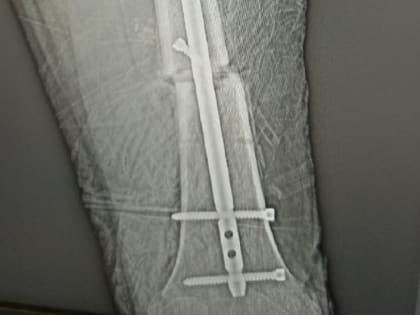

В Волгограде 17-летнему мотогонщику дважды «собрали» ногу из осколков

В Волгограде травматологи БСМП № 15 провели сложнейшую операцию на нижней конечности 17-летнему байкеру.